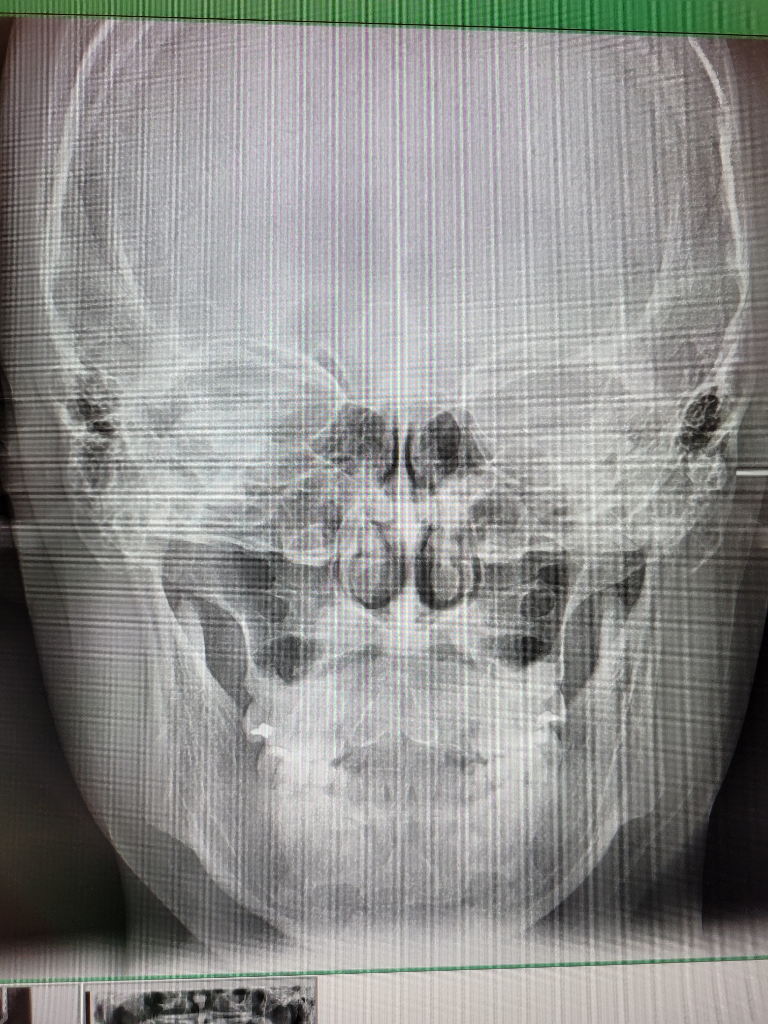

• 3번 째 사진

안녕하세요. 구강악안면외과랑 교정과 돌아봤는데 절단교합인 3급 부정교합이 있고 어금니가 잘 맞지 않는 상태라면서 돌출입 경향에 거미스마일이 있다는 진단과 함께 미세한 비대칭(3mm정도 가량)과 턱끝이 7~8mm(이마뼈 기준 턱 끝이 5mm들어간 위치를 정상으로 볼 때)가량 나왔다는 진단을 받았습니다. 그러면서 발치가 동반되는 돌출입 교정을 하면 주걱턱스러운 부분이 어느정도 개선되지만 중안면부 함몰 및 주걱턱에서 나타나는 중안모가 꺼져서 나타나는 특유의 이상한 느낌에 대한 개선과 하악이 전돌된 부분에 대한 제대로 된 개선​은 어렵다고 했습니다. 그 외의 방법으로의 주걱턱 교정은 외모 개선의 효과는 전혀 없고 교합만 맞춰진다고 했습니다. 그러면서 확실한 외모 개선(중안면부 함몰에 대한 개선과 하악이 전돌된 부분에 대한 개선)을 원한다면 상악의 발치교정으로 위턱이 들어간 상태에서 위턱을 전체적으로 전방이동하는 수술방식 혹은 양악 회전술(전문 용어로 clockwise rotation of maxilla mandibular complex, 이 술식의 경우 하악이 너무 뒤로 이동할 가능성이 높은 술식)과 더불어 이부성형술을 교합만 맞추거나 돌출입만 들어가는 정도로 생각한다면 교정을 생각해보라는 이야기를 들었습니다. 저는 확실한 외모 개선(중안면부 함몰에 대한 개선과 하악이 전돌된 부분에 대한 개선​)을 원하지만 양악수술은 구강악안면외과의 수술 중 비교적 큰 수술에 속하는 만큼 신중히 결정하고자 합니다. 우선 안모, 교합, x-ray 사진자료를 올릴 테니 수술 케이스, 보더라인, 수술 정말 필요없는 케이스 중 어디에 속하는지 대략적인 판단을 부탁드립니다. 선생님 다시 한 번 말씀드리지만 저는 확실한 외모 개선(특히 중안면부 함몰에 대한 개선​)을 원합니다!!!